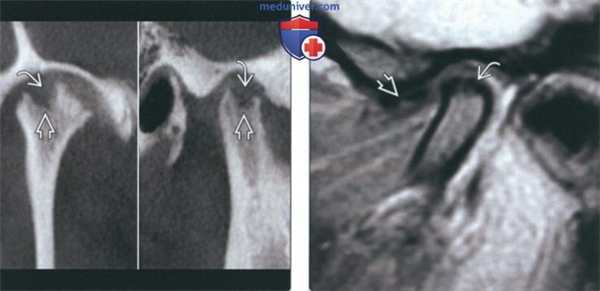

(Слева) На реформатированных под углом корональном и сагиттальном изображениях (КЛКТ) отсутствует кортикальная пластинка со стороны верхнего края мыщелка, формируется полость в субхондральной кости, мыщелок уменьшен в размерах. Эти изменения означают активную стадию ДЗС.

(Справа) На косой сагиттальной MPT (Т1 ВИ FSE) визуализируется маленький мыщелок с толстым гипоинтенсивным ободком вдоль передней поверхности. Диск находится спереди от мыщелка (при закрытом рте). Это стабильная ДЗС в завершающей фазе.